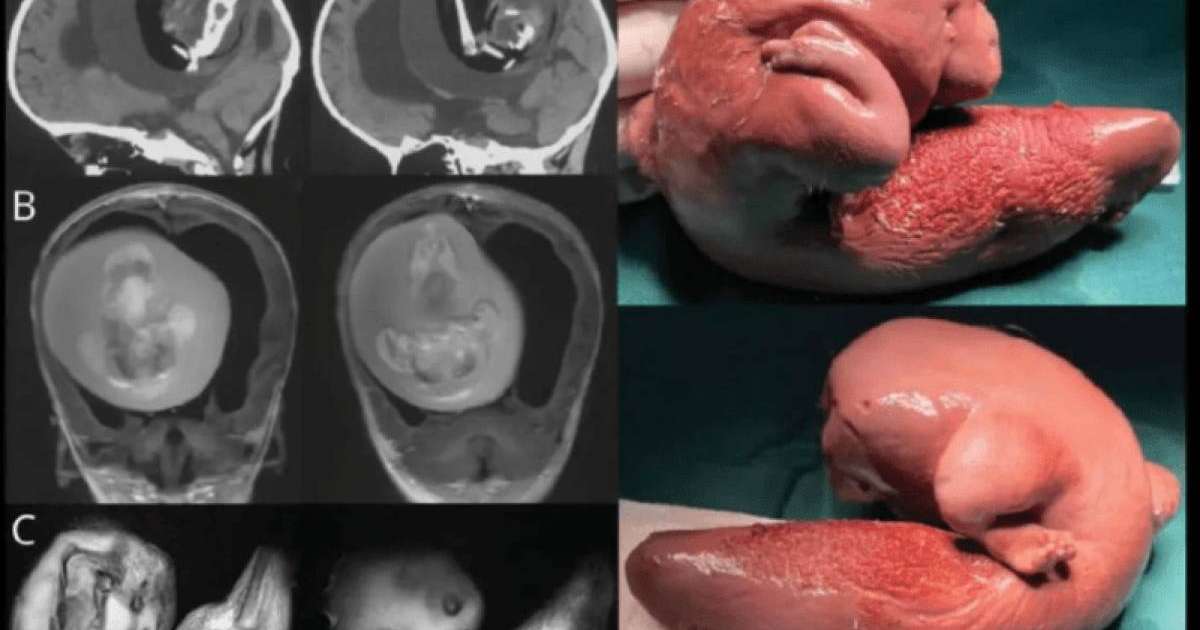

Қытайлық хирургтар бір жасар қыздың миынан егізінің ұрығын алып тастады деп хабарлайды Kznews.kz ақпарат агенттігі Gazeta.ru сайтына сілтеме жасап.

Қыздың ата-анасы баланың басы үлкейіп, моторикамен қиындықтары пайда болғанын байқап, ауруханаға апарады. Нәтижесінде оның миында 10 см-лік ұрық бар екені анықталды.

Дәрігерлердің айтуынша, ұрық өсіп, аяқ-қолдары мен сүйегі, тіпті тырнақтары өскен. Бұл ұрық қан айналым жүйесі мен қыздың қан айналым жүйесінің бірігуіне байланысты болуы мүмкін.

Медицинада “ұрық ішінде ұрық” деген термин бар. Бір ұрық екіншісінің денесінде өседі. Әлемде 200-дей осындай жағдай орын алған. Ұрық ауыз қуысы, жамбас, ішек жолдарында анықталады. Осы уақытқа дейін 18 адамның миында егіз ұрық табылды. Нәрестелерден бөлек, тіпті ересек болған кезде де бұл анықталып жатады.